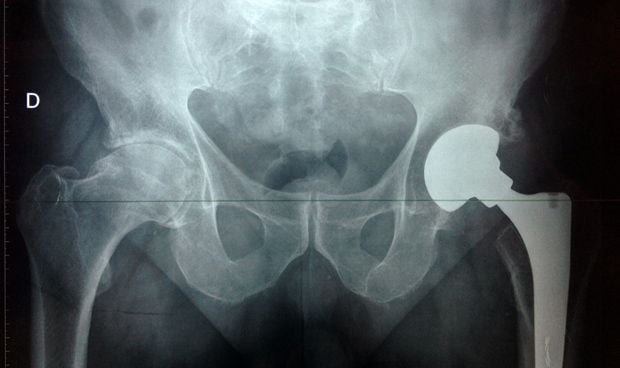

El dispositivo inicialmente ha sido diseñado para aplicarse en exo-prótesis de fémur y húmero.

Investigadores de la Universidad Politécnica de Valencia (UPV), en colaboración con el Hospital Clínico Universitario de Valencia-Incliva y la Universidad de Valencia (UV), han desarrollado un collar percutáneo que permitiría reducir el riesgo de infecciones en implantes de prótesis de fémur y húmero, así como en la realización de ostomías.

"El dispositivo inicialmente fue diseñado para aplicarse en exo-prótesis de fémur y húmero pero, al garantizar un sellado de la comunicación, permite su utilización en todo tipo de estomas de derivación como colostomías, cistotomías, entre otras", señala Antonio Silvestre, investigador de la UV y del Incliva.